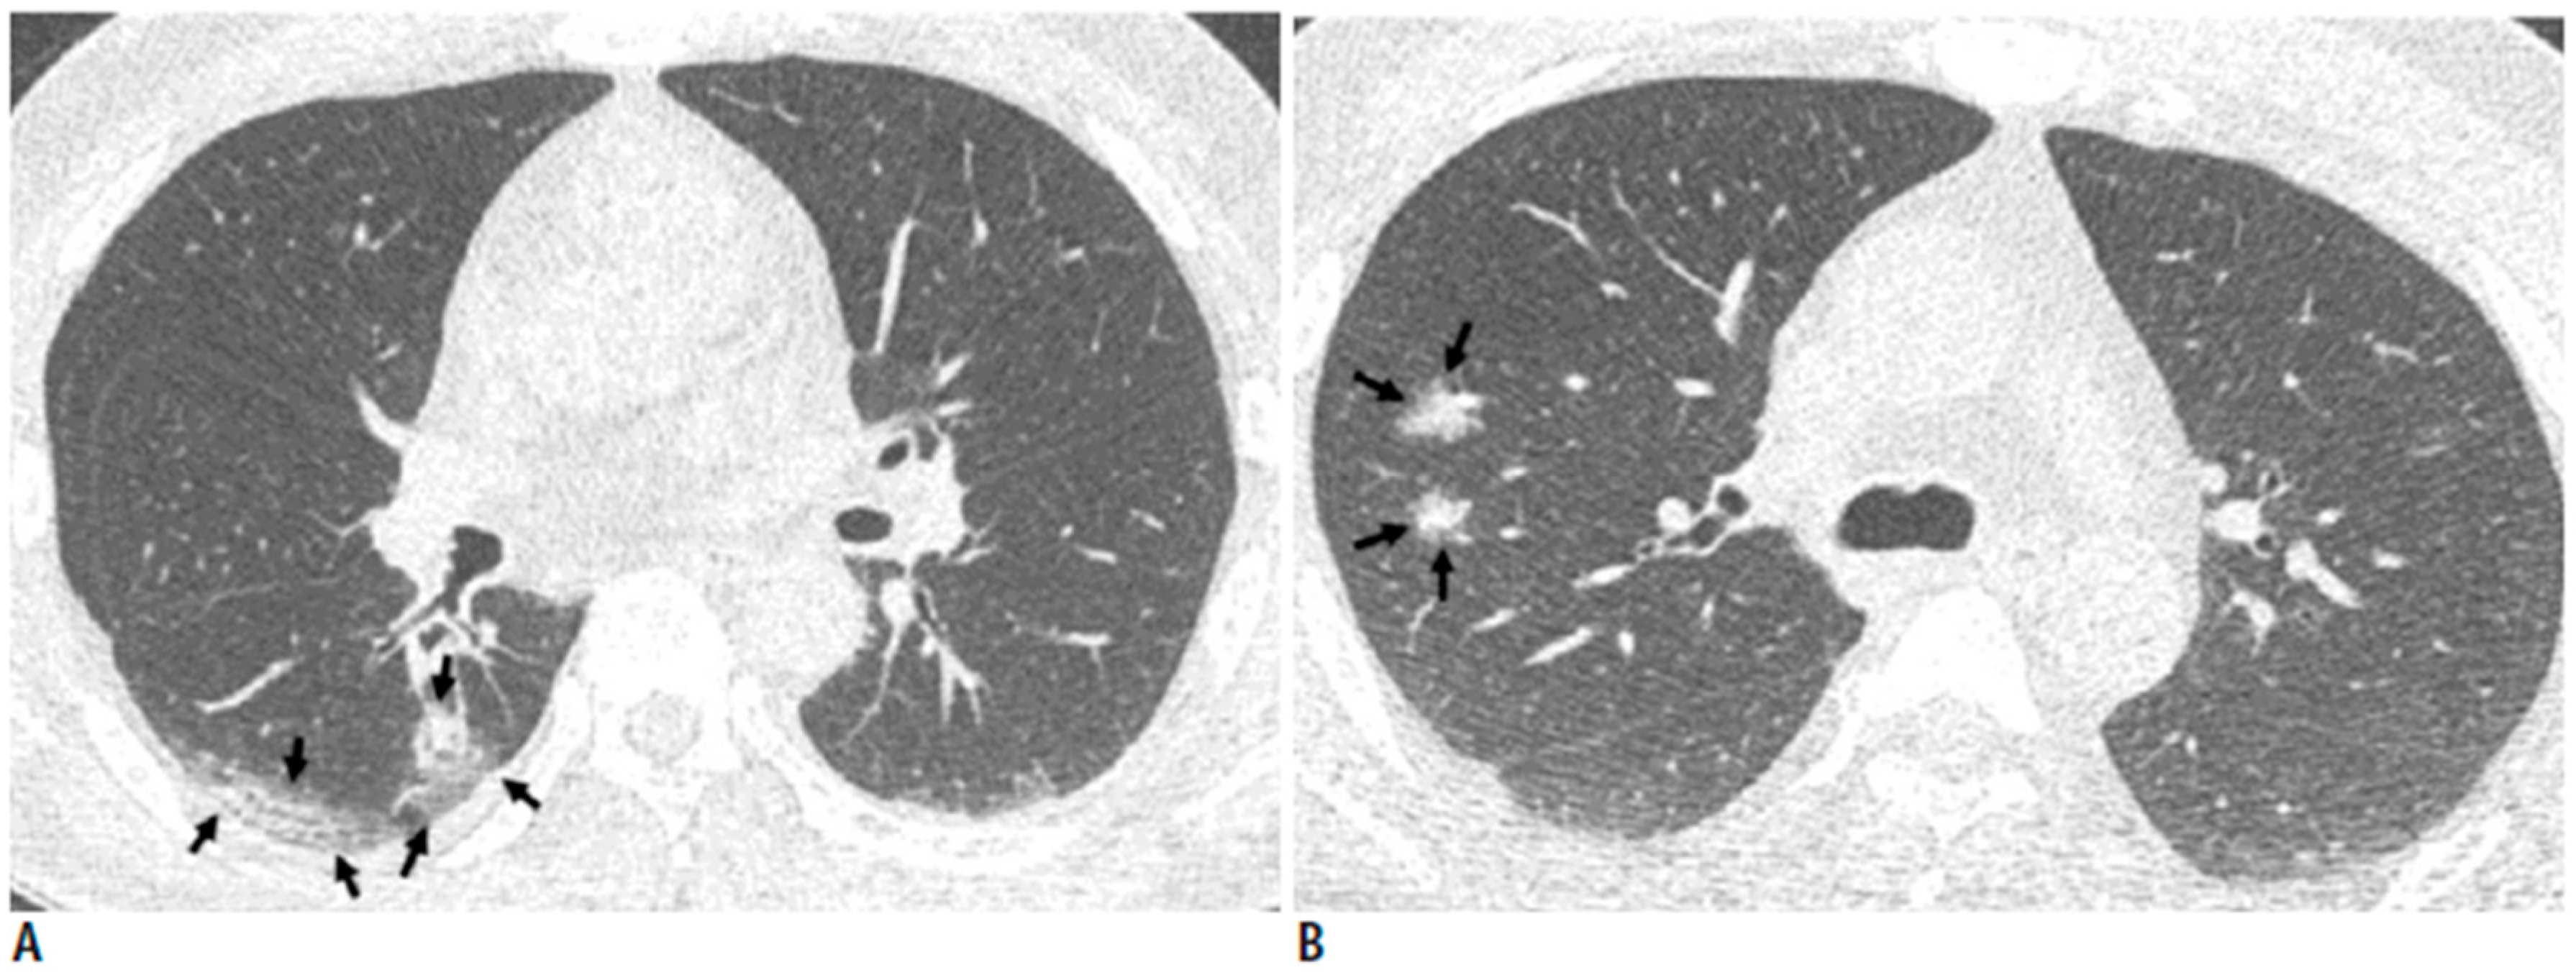

3.3. Case C